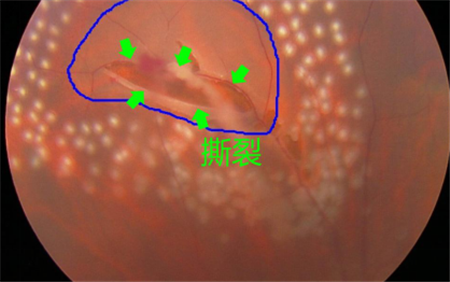

視網膜退化以及撕裂、后玻璃體脫落、葡萄膜炎、糖尿病或者黃斑變性引起的眼底出血等,可導致飛蚊癥產生,這種情況就屬于惡性飛蚊。雖然飛蚊本身并不會導致眼睛失明,但這些原發(fā)疾病若不及時治療,失明的風險卻是非常大的。

所以在出現飛蚊癥時,建議上醫(yī)院做個檢查,看看屬于哪一種飛蚊。尤其是突然出現大量飛蚊、閃光,并伴隨視力下降或者視野缺損的情況,更需要及時就醫(yī)。在北京希瑪林順潮眼科醫(yī)院治療惡性飛蚊需要結合患者的原發(fā)疾病進行治療,比如由視網膜裂孔導致的飛蚊癥,需要通過激光治療將裂孔封閉,從而避免視網膜進一步脫落。